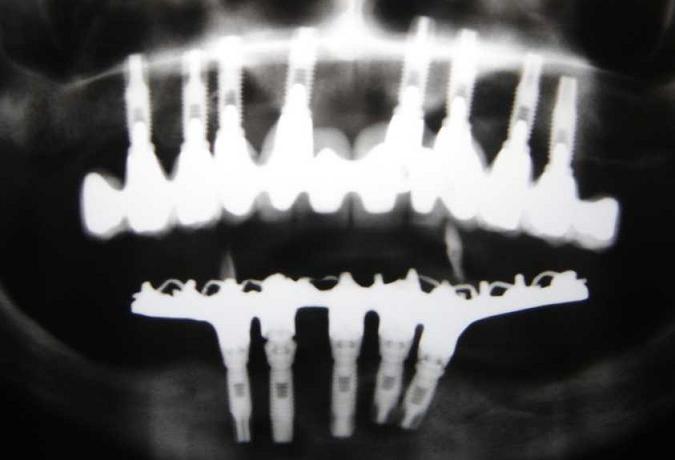

IMPLANTES SUPERIORES INSTALADOS APÓS O ENXERTO ÓSSEO E IMPLANTES INFERIORES

PRÓTESE FIXA SUPERIOR SOBRE IMPLANTES APÓS ENXERTO ÓSSEO

PRÓTESE FIXA INFERIOR PROTOCOLO